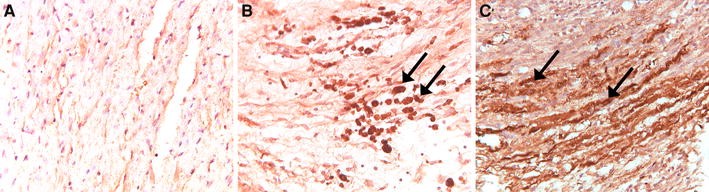

Immunohistochemical staining of sPLA2-IIA expression in the rat heart after AMI. No sPLA2-IIA expression was found on cardiomyocytes 28 days after AMI in both the vital (a) en the infarcted (b) area. sPLA2-IIA expression was found in inflammatory cells in the infarction area (b, see arrows). c As a positive control, at 5 days post AMI, sPLA2-IIA depositions were found on jeopardized cardiomyocytes in the infarction area in untreated AMI rats (arrows). Magnification a, b, c: 200×